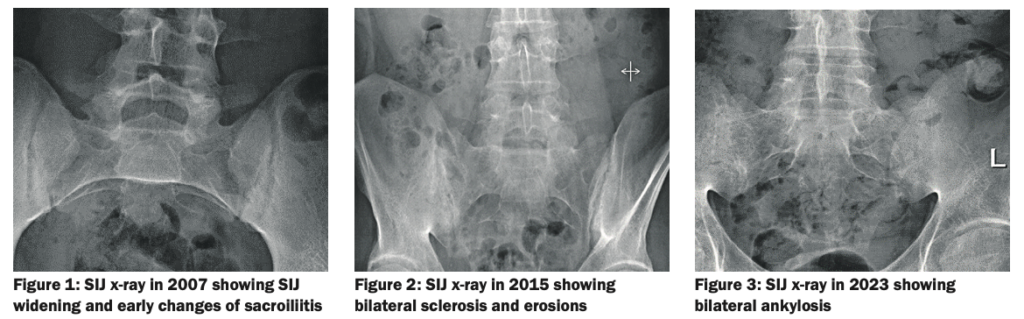

Recent investigations showed normal full blood count, renal and liver profile with a raised CRP of 10mg/L, and erythrocyte sedimentation rate (ESR) of 21mm/hr. HLA-B27 was positive. On a review of previous pelvic x-rays, radiographic progression can be seen between 2007 (Figure 1) showing SIJ joint widening, and 2015 (Figure 2) showing SIJ sclerosis and erosions, and 2023 showing bilateral SIJ fusion (Figure 3).